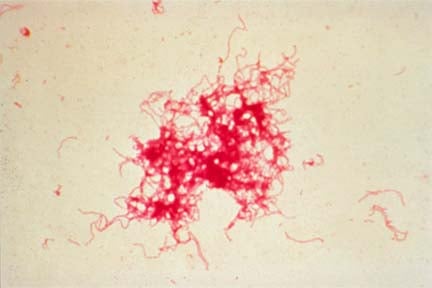

Az étrend folyékony-pépes, majd rost- és fűszerszegény változata lényegében a Meulengracht-diéta, amelyet vérzés után alkalmazunk. Alapelve: mennél nagyobb a vérzés, annál nagyobb a beteg étel- és italszükséglete. A beteget nem koplaltatjuk, hanem a vérzést követő napon öt étkezésben energiában, fehérjékben és vitaminokban kielégítő, folyékony-pépes étrendet adunk.Fekélybetegségben nemcsak a beteg szerv, hanem a betegség folytán legyengült szervezet, az egész ember gyógyítása a cél. A rossz emésztés, a felszívódási zavarok megváltoztatják a betegségben szenvedők tápanyagszükségletét. A táplálékban elegendő fehérjét: testsúly kilogrammonként 1,2-1,5 g-ot kell bevinni. Hasonló mennyiségben kell adni a zsírt is. Szénhidrátból Sg/testsúly kg az igény. Vitaminokból a normál vitaminmennyiség többszöröse a szervezet szükséglete.Az ételek fogyasztásánál különösen ügyelni kell a gyakori kis étkezésekre. Kezdetben a kétóránkénti étkezések, később is a napi hét-, ill. hatszori étkezés kívánatos. Helyes az elalvás előtti étkezés, hogy a gyomor az éjszaka folyamán ne álljon üresen. Ugyancsak ajánlatos a betegek éjjeliszekrényére éjszakára is piskótát, kekszet, egy pohár tejet helyezni, hogy ha felébred éjszakai étkezésre is legyen lehetősége.